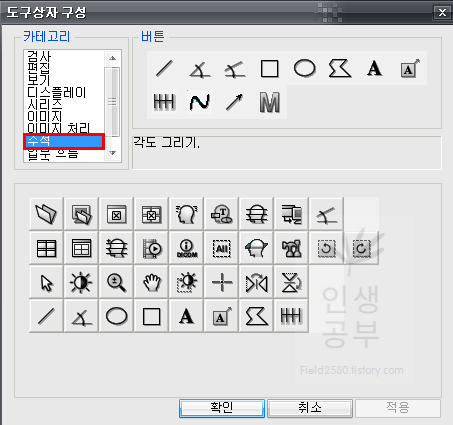

위와 같은 도구상자 구성 화면이 뜨게 됩니다. 아래에는 현재 사용중인 도구상자들이고 왼쪽 상단에는 도구상자에 넣을 수 있는 카테고리들이 있습니다. 카테고리칸 옆에는 버튼칸이 있고 아래 도구상자칸에 없는 메뉴들도 많이 있습니다. 아이콘에 마우스를 가져다 대면 간단한 설명이 나오니 필요하신 분들은 한번씩 다 확인해보시는 걸 추천해드립니다.

저 같은 경우는 Cobb 각도를 많이 사용하기 때문에 우선 Cobb각도 설정하는 방법에 대해서 알려드리겠습니다. 카테고리칸에 주석을 눌러주면 다양한 각도나 선, 모양을 그릴 수 있는 버튼이 나옵니다. 그중 상단 3번째 있는 버튼이 Cobb각도 그리기 입니다.

저 같은 경우는 선을 그리는 버튼도 많이 사용하니 추가해 줍니다.

카테고리에서 주석 메뉴를 클릭하면 오른쪽 버튼칸에서 2번째줄 2번째에 있는 것이 선그리기입니다. 위와 같은 방법으로 아래 도구상자란에 마우스로 끌어서 추가해줍니다.